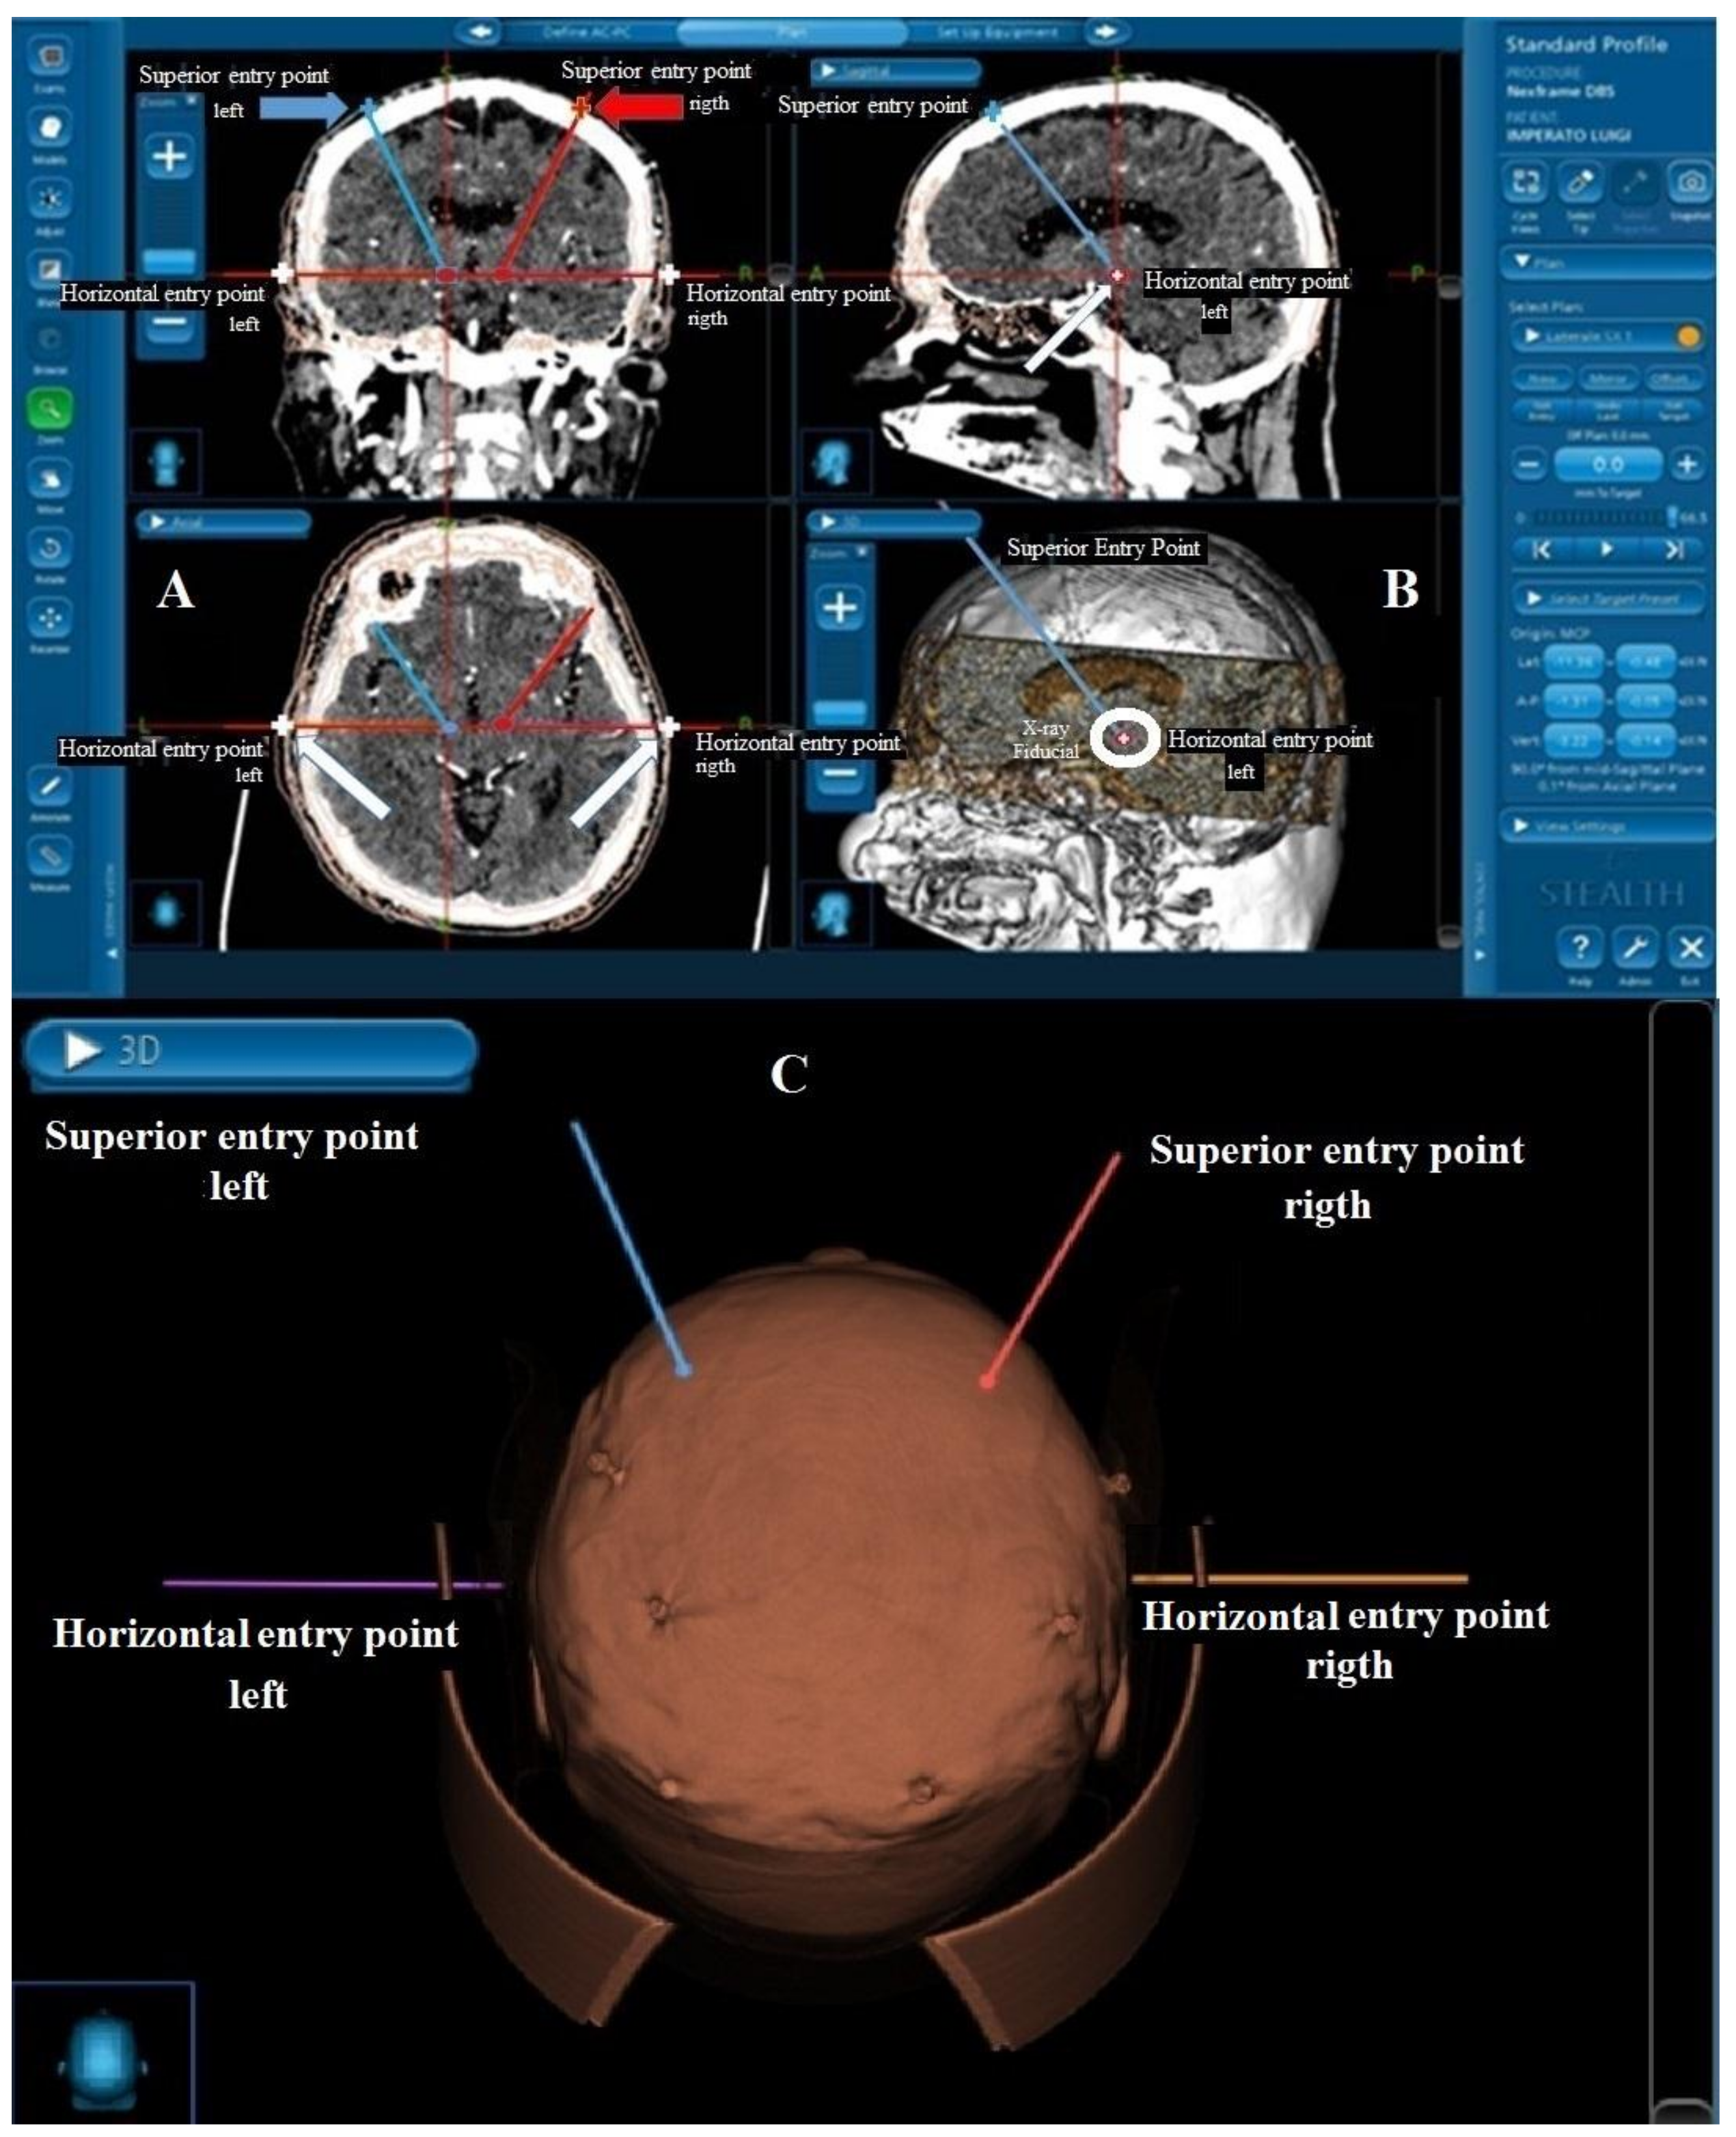

The Stealth computerized system for image fusion (Medtronic Stealth-Station Framelink® Software package) was employed using angio-CT scan images taken the day before surgery and fiducial marker screws (Medtronic, Minneapolis, MN, USA) applied to the skull. Fusion images were obtained from 1 mm thick angio-CT scan slices and from T1- and T2- weighted MRI slides Traditional coordinates and trajectories were adopted to target the STN, i.e., 12 mm lateral with respect to the midline for the X coordinate; −2 mm with respect to the midcommissural point (also taking into account the individual anatomo-radiological variability) for the Y coordinate, and 4 mm below the Ca–Cp line for the Z coordinate. The planned trajectories were always extraventricular and the superior entry point of the electrodes was checked in the surgical space using the facility that the Nexframe offers to verify the inclination of the electrode trajectory. Particular attention was paid to the angiographic representation of cortical vessels to ensure that there was no conflict between the electrode trajectory and vessels. Once the two STN targets and their representation on the axial CT/MRI fusion images had been located, a bilateral horizontal entry point that corresponded to the z coordinate of the two electrodes along a horizontal line was added to the established surgical plan (Figure 2).

Figure 2.

(A) Coronal (upper) and axial (lower) CT scan slides. The trajectories and superior entry points (red/blue arrows and red/blue cross) planned using the Medtronic Stealth-Station Framelink software package are reported. The inclined blue line represents the trajectory targeting the left STN, while the inclined red line represents the trajectory for the right STN. The horizontal red line crossing the target points from right to left is the Z plane. When this line crosses the skin (white arrows and cross) it is easy with the neuronavigational system to establish the horizontal entry point corresponding to the target point; (B) That which is reported in (A) is here represented in sagittal view. The projection of the horizontal entry point is represented by the red dot (white arrows and white cross inside the red dot). The inclined blue line represents the trajectory of the electrodes (upper slide); in (B), lower slide, a X-ray visible fiducial (white circle) is reported. (C) The 3D representation of the surgical planning and fiducial screws.